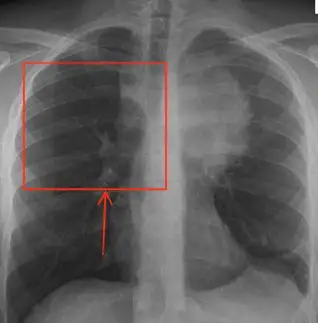

The anteroposterior chest x-ray reveals a large, ovoid mass located just left of the midline, appearing inseparable from the mediastinum. The pulmonary hila and aortic contour remain visible, and the lateral view (not shown) confirmed a clear posterior chest, suggesting the mass is confined to the anterior mediastinum. The anterior mediastinum is located anterior to the pericardium and inferior to the clavicles.

The differential for such a mass is classically remembered by the “4 Ts”:

- Thymoma

- Teratoma/Germ Cell Tumor

- Thyroid mass

- “Terrible” Lymphoma

A contrast-enhanced chest CT is the recommended next diagnostic step. CT imaging provides superior anatomical detail, delineating the size, location, and involvement of adjacent structures—critical for determining etiology and guiding further management. Evaluation should also include assessment for possible extra-thoracic involvement, such as testicular masses in suspected germ cell tumors.